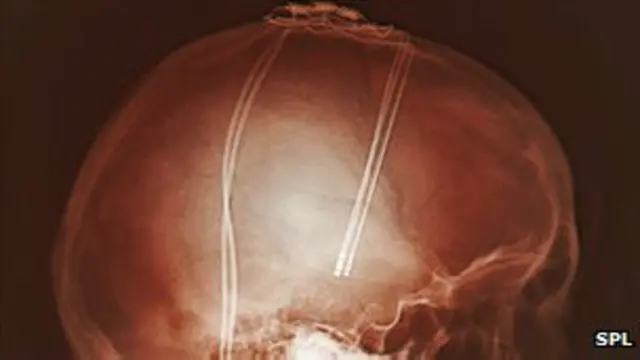

La estimulación cerebral intenta normalizar esa actividad por medio de una serie de impulsos eléctricos que se dirigen a la parte afectada del cerebro con un dispositivo operado por una batería, llamado neuroestimulador, similar a un marcapasos cardíaco.

"La cirugía involucra hacer dos incisiones muy pequeñas en la región frontal del cráneo y a través de éstos se introducen dos electrodos en el cerebro" explica el doctor Espinoza.

"La cirugía se realiza guíada por computador de forma muy precisa para minimizar el trauma de los tejidos. Como toda cirugía tiene un grado de invasividad, pero lo estamos reduciendo día a día y esperamos optimizarla aún más en el corto plazo" señala el neurocirujano.